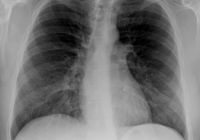

Vengono eseguite radiografie di tutto lo scheletro, del torace e dell'addome.